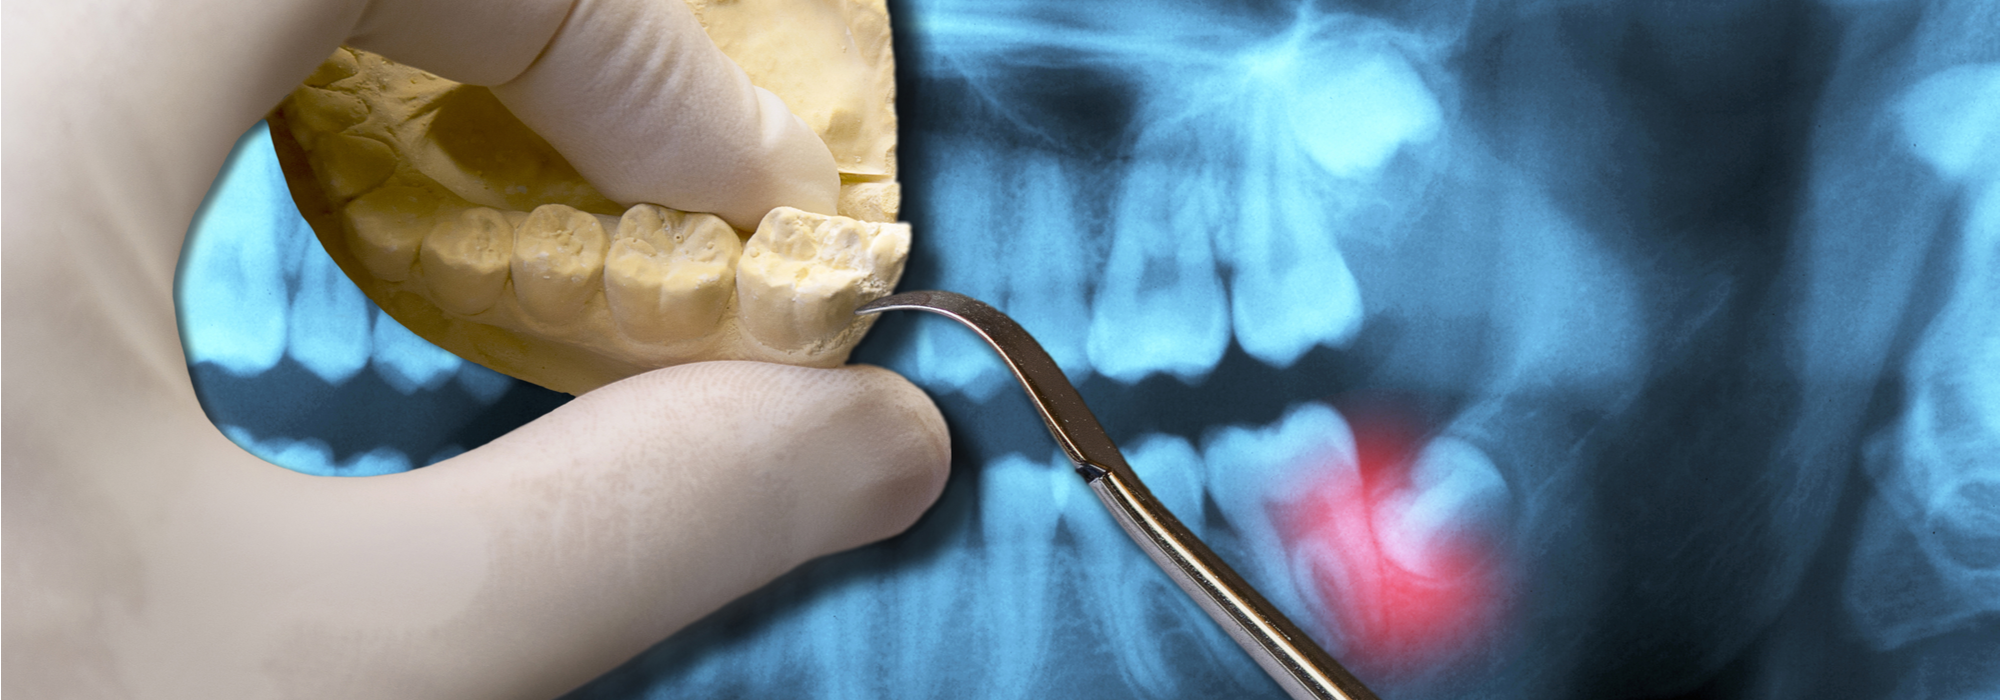

ORAL EXAMINATION FOR EXTRACTION OF WISDOM TEETH

With an oral examination and x-rays of the mouth, Dr. Kunal Rajyan and can evaluate the position of the wisdom teeth and predict if there are present or future potential problems. Studies have shown that early evaluation and treatment result in a superior outcome for the patient. Patients are generally first evaluated in the mid-teenage years by their dentist, orthodontist, or by an oral and maxillofacial surgeon.